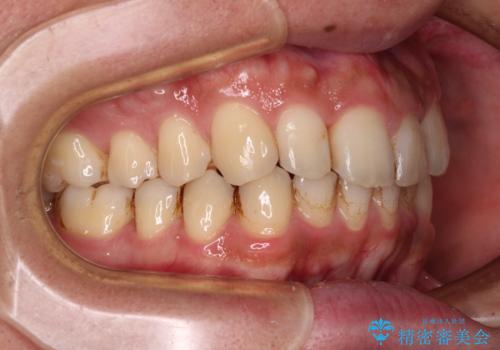

前歯のデコボコをスッキリ改善 インビザライン矯正

- 上下前歯のデコボコを気にして来院された患者様です。

全体的に叢生は軽度であったため、インビザラインにて矯正治療を行うこととしました。

デコボコの改善はもちろん、下顎前歯が隠れてしまうディープバイトも一緒に改善することができ、奥歯への負担を軽減することができました。